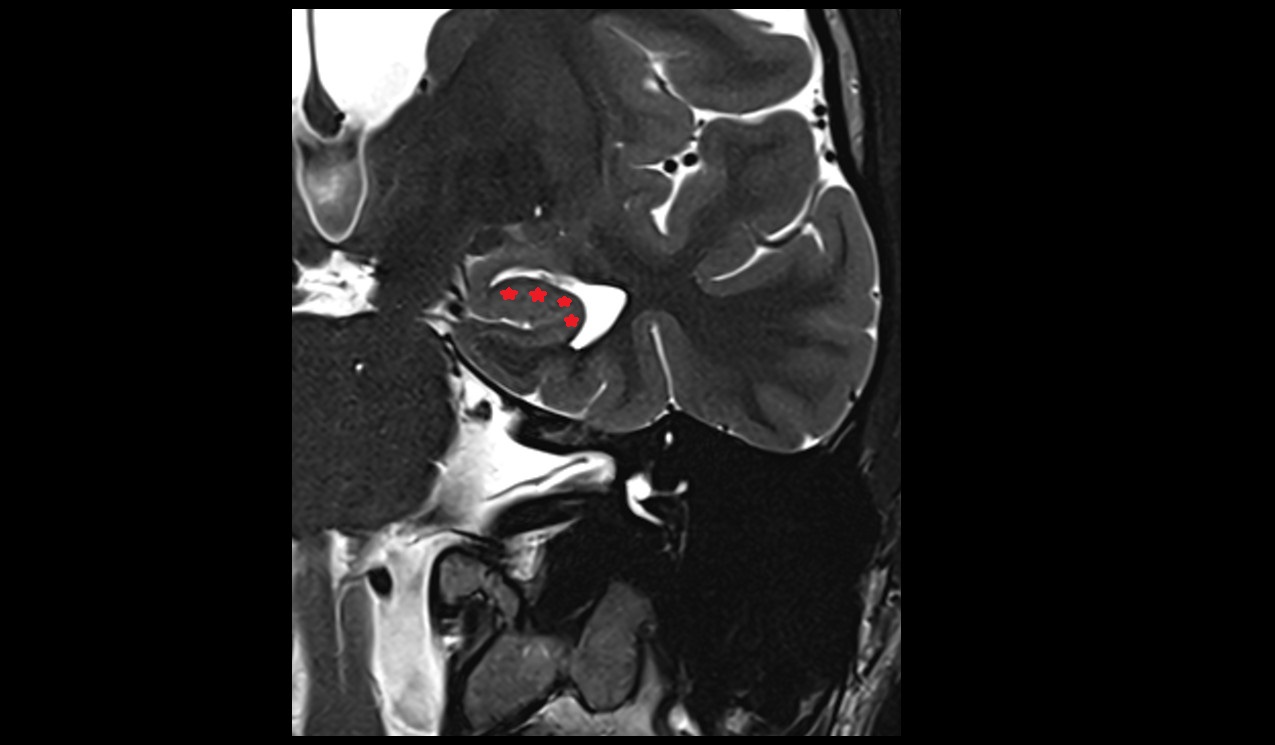

- Body of hippocampus

- Head of hippocampus

- Tail of hippocampus

- Hippocampus